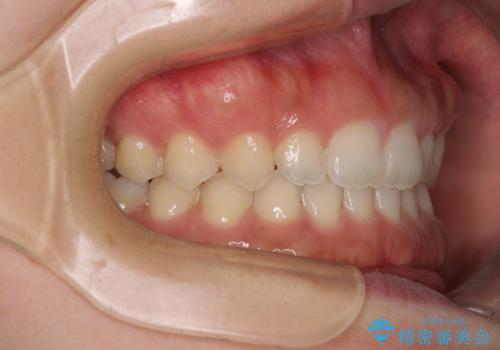

気になる隙間の再矯正 前歯をインビザライン・ライトで改善

- 後戻りによる上下前歯の隙間を気にして来院された患者様です。

歯列不正はそれほど大きくなかったため、インビザライン・ライトを用いて矯正治療を行うこととしました。

無理のないペースで治療を進め、9ヶ月で終えることができました。